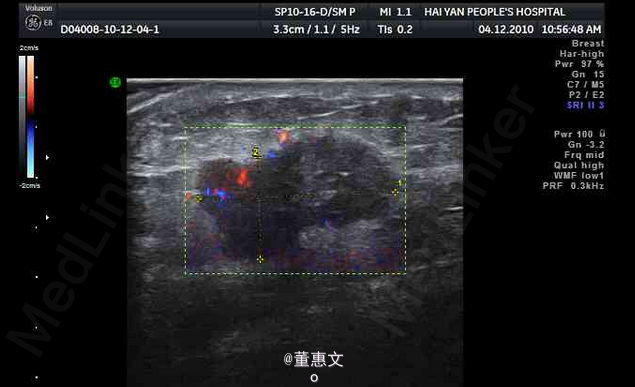

女,50岁,因3月前无意中发现右侧乳腺外下象限肿块前来就诊

无疼痛及皮肤破溃,活动度差,五畏寒发热。无胸痛及其他不适。 辅查超声

右乳腺癌 处理:手术配合放疗化疗